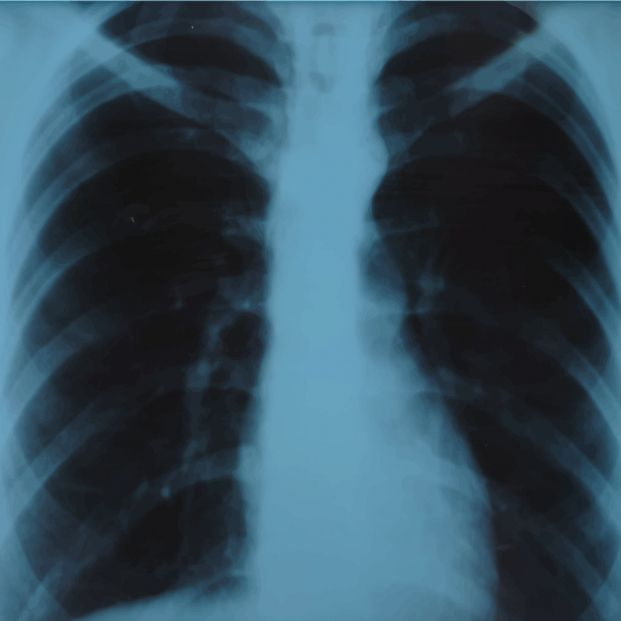

El futuro ha llegado. Gracias a una Inteligencia Artificial, investigadores norteamericanos son capaces de predecir el riesgo de muerte de una persona, haciendo uso de una única radiografía del tórax. Lo que hace unos años sería pura ciencia ficción, hoy se hace realidad gracias al desarrollo del aprendizaje en profundidad que utilizan este tipo de tecnologías novedosas.

Este modelo, presentado este martes 29 de noviembre en la reunión anual de la Sociedad Radiológica de América del Norte (RSNA), realiza una estimación a 10 años vista. Lo que calcula esta IA es la probabilidad de que el paciente sufra un ataque cardíaco o un derrame cerebral mortal debido a la acumulación de grasas y colesterol en las arterias, que se conoce de forma técnica como enfermedad cardiovascular aterosclerótica.

La principal mejora, que proporciona numerosas posibilidades, es que ahora solo se necesita una radiografía, que se adquiere millones de veces al día en todo el mundo, para realizar estas predicciones.